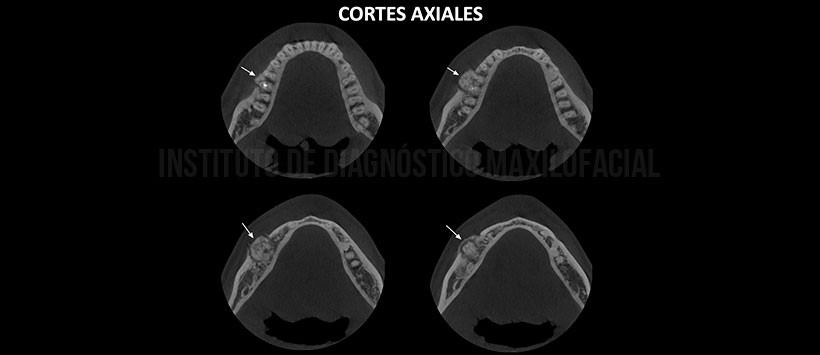

A la evaluación de la tomografía volumétrica (CBCT) cortes axiales (Figura 2), transaxiales (Figura 3) y tangenciales (figura 4) se aprecia imagen hiperdensa con pequeños focos isodensos delimitada por un halo hipodenso, localizado a nivel periapical de la pieza 46, que se fusiona con el tercio apical de la raíz mesial y distal; ocasiona el desplazamiento, adelgazamiento y erosión de la tabla ósea vestibular.